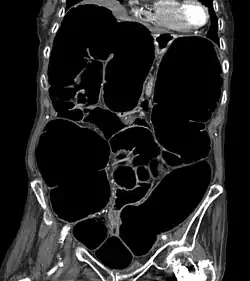

Die Diagnostik der Erkrankung ist einfach, da das Röntgenbild sehr charakteristische Zeichen aufweist. Der gesamte Dickdarm ist breit mit Luft gefüllt, vor allem der aufsteigende Teil des Dickdarmes erreicht eine Breite von oft mehr als 10 cm.

- Computertomografie des Abdomens